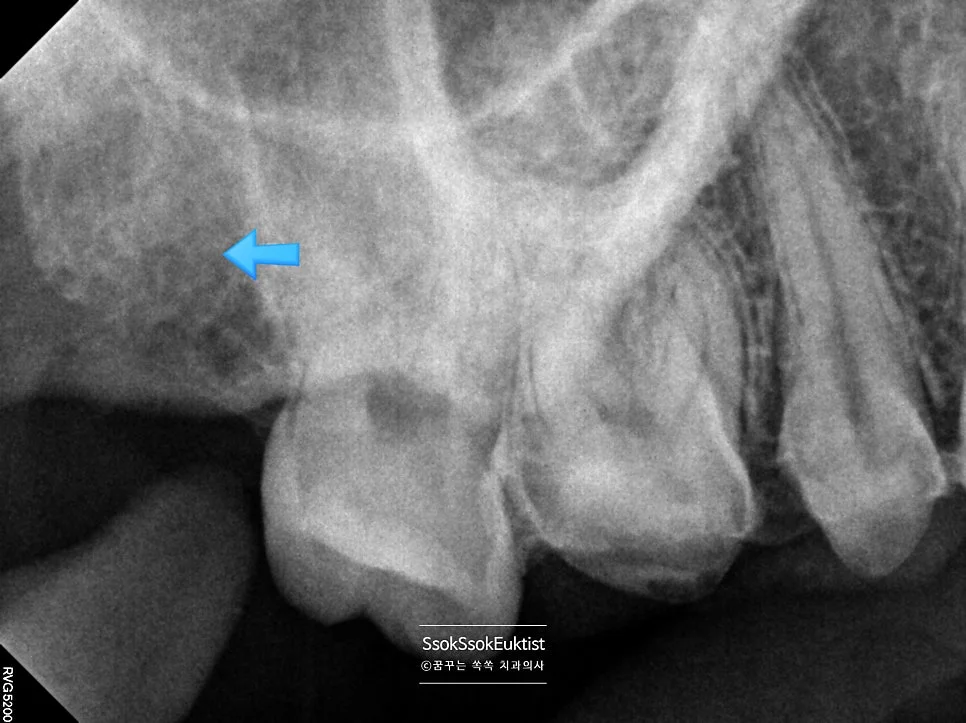

치아 사이 충치는 인접하여 붙어 있는 치아 때문에 접근이 제한되어 최소한 인레이 치료가 필요합니다. (영역이 큰 경우 크라운 치료가 필요함)

화살표의 충치를 치료하기 위한 치아 삭제 과정

화살표의 충치를 치료하기 위해 사진에서의 모양처럼 상당한 양의 치아 삭제가 필요한 거죠ㅜ

한편 치아 사이 충치는 하나의 치아에서만 생기지 않고 인접한 치아와 함께 생기는 경향이 있는데요. 치아 사이에 음식물이 저류하고 세균이 살면서 생기는 충치이기에 어찌 보면 당연하겠죠ㅜ

그래서 치료를 하다 보면 인접한 치아의 모습을 육안으로 바로 확인할 수 있는데요.

인접 치아 충치 확인 — 위 화살표의 충치는 굳이 치료가 필요하지 않은 충치

위에 화살표의 충치는 굳이 치료가 필요하지 않은 충치이고요.

이 화살표로 표기된 충치는 치료가 필요한 충치입니다.

이렇게 인레이 혹은 크라운 치료를 할 때가 인접면 충치에 접근 가능한 유일한 시점인데요. 이때 인접면 충치를 치료하게 되면 접근이 용이하므로 충치 부분만 딱 레진으로 때우고 치료를 마무리할 수 있습니다.

1번 치아의 경우 2번 치아의 치료가 종료된 후에 충치가 커져 치료를 원하게 될 때에는 레진 치료가 아니라 인레이 치료가 필요한 것이죠ㅜ 그래서 지금 함께 치료하는 것이 치아 삭제량과 비용 모두에서 유리합니다.